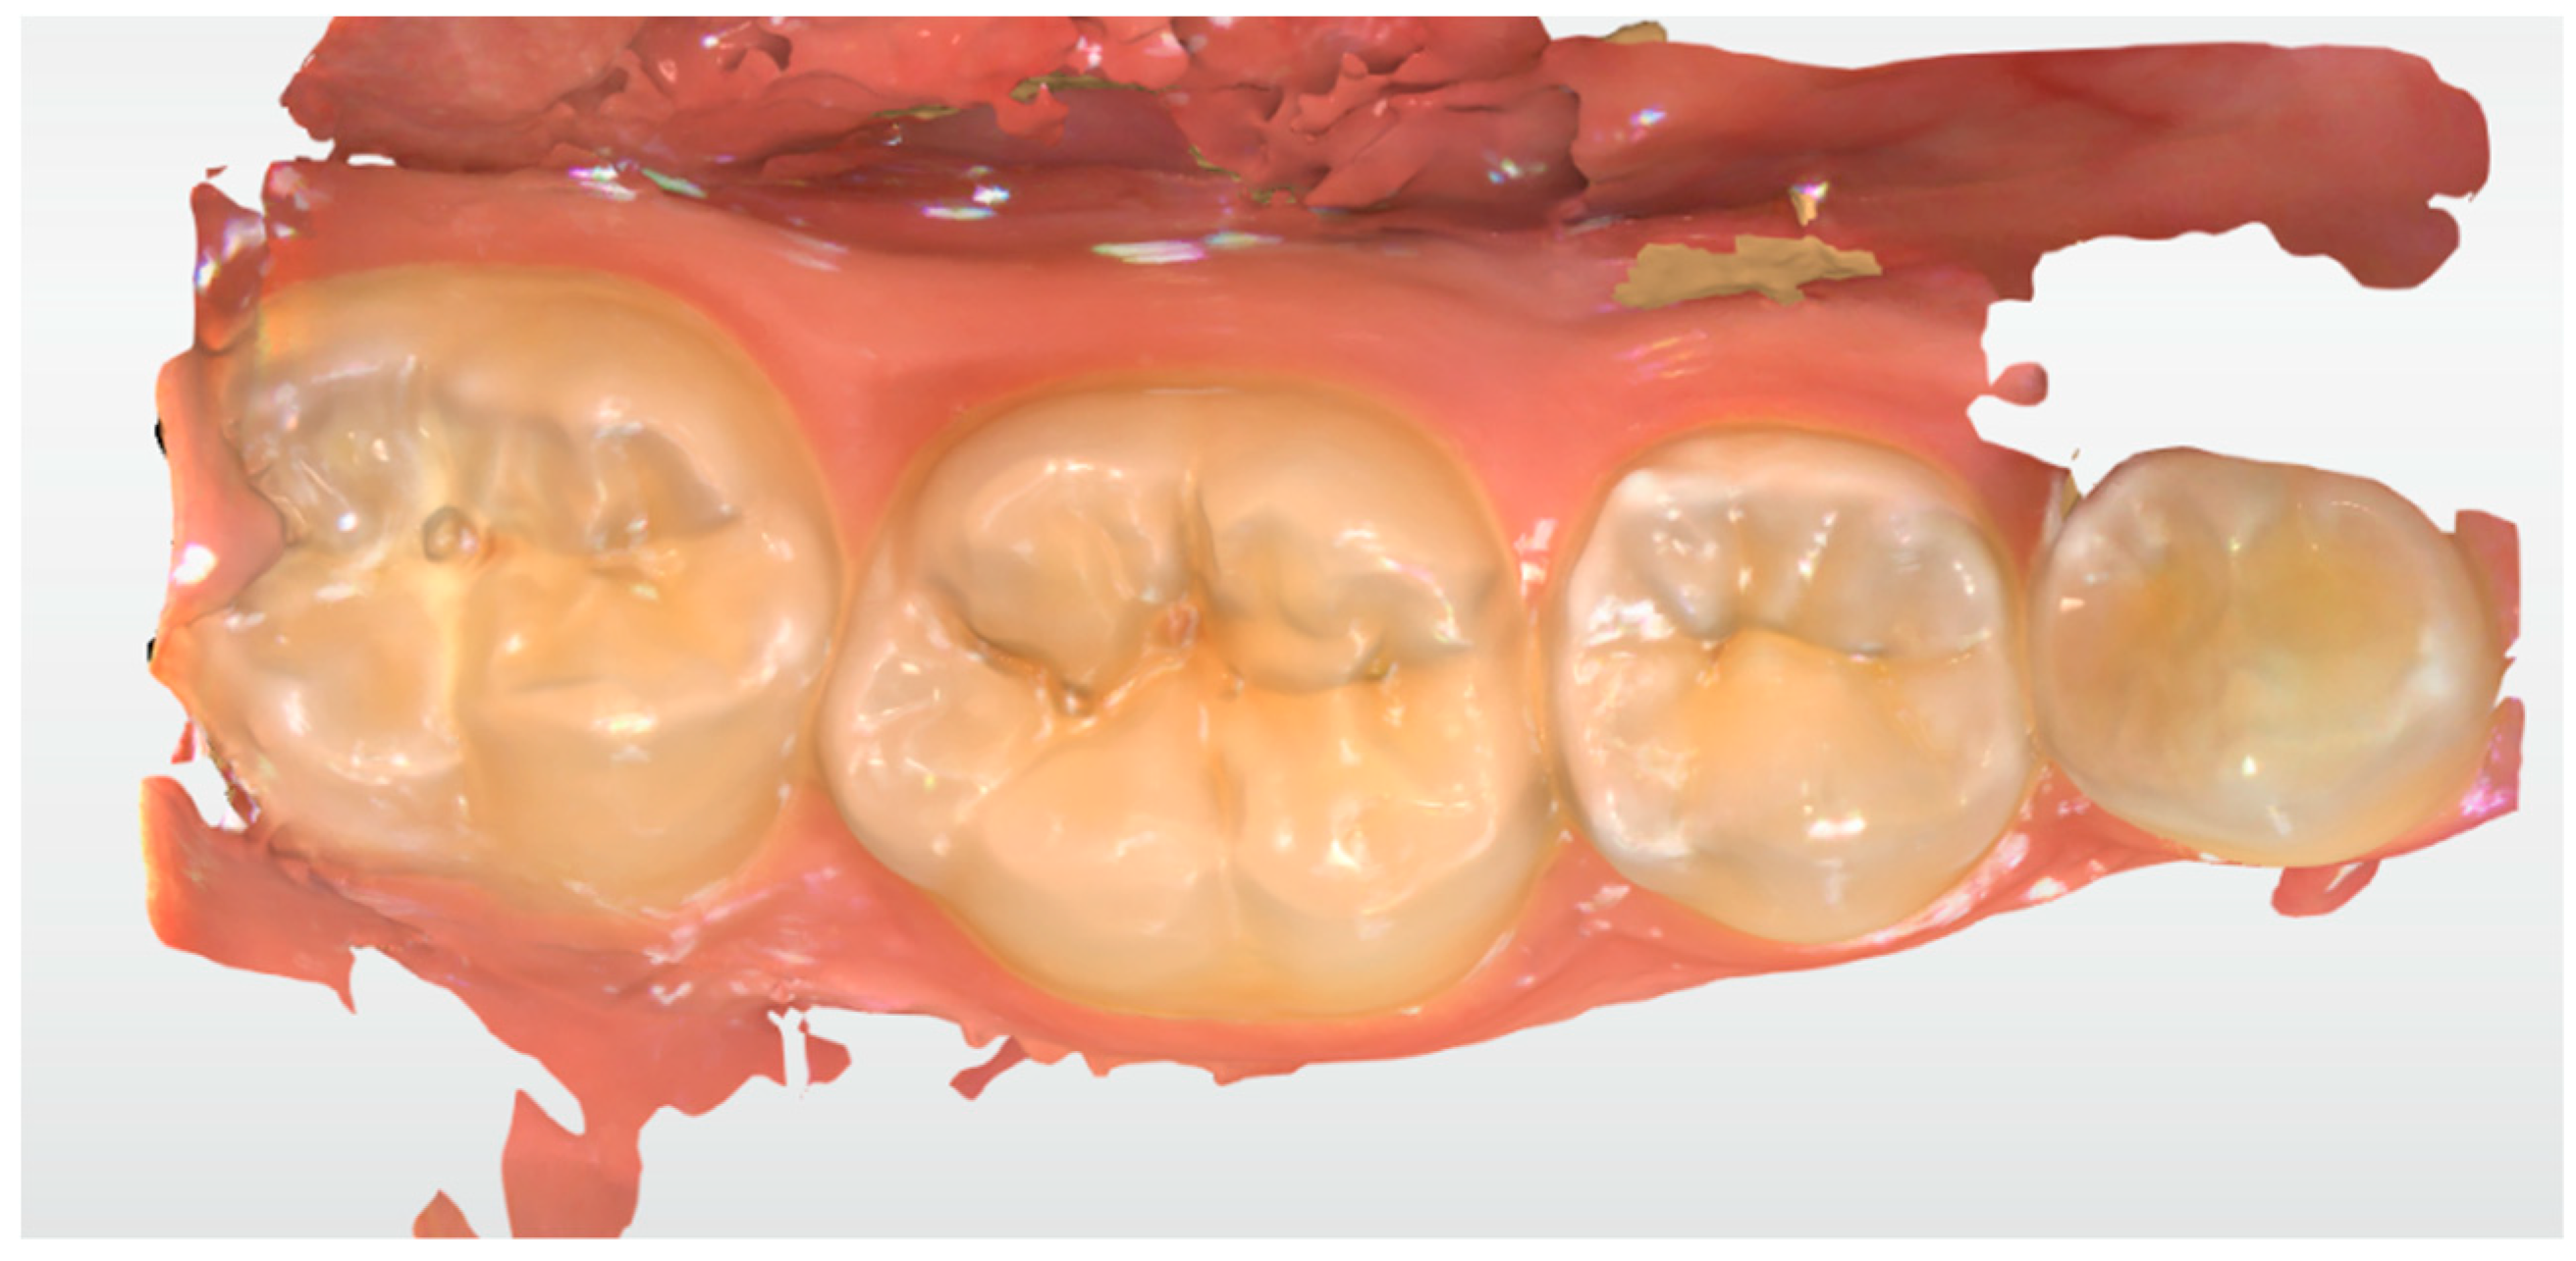

2.2. Clinical Case